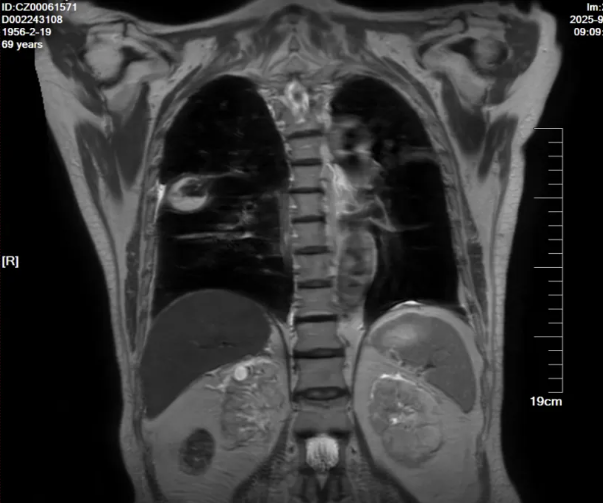

2025年8月31日,患者进食后出现严重恶心、呕吐等胃肠道反应,伴肝酶升高,经予止吐、护胃、静脉营养支持及保肝治疗后未见好转,考虑为复方磺胺甲噁唑片不良反应,遂将其剂量逐步减量至0.48g bid后患者胃肠道反应减轻。2025年9月1日复查血液指标提示BNP及D-二聚体升高,加用利尿、抗凝等对症治疗;复查胸部CT(见图4)显示右肺上叶空洞性病变及右肺下叶背段结节较2025年8月15日影像明显缩小,提示当前抗感染治疗方案有效。

图4.胸部CT(25-8-15 vs 25-9-1)

-胸部增强MRI(2025-9-2):1.右肺上叶后段病变(右肺上叶后段见一类圆形异常信号影,大小约3.3x2.7cm,T2WI及抑脂序列呈高低混杂信号,DWI上见弧形高信号影,增强扫描呈环形强化)。 2.双肺散在炎症,部分肺不张。 3.双侧胸腔少量积液。

图5. 胸部增强MRI (2025-9-2)